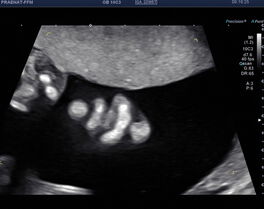

Organscreening (Fehlbildungsausschluss)

Diese „zweite“ große Ultraschalluntersuchung wird am besten in der 20+0 SSW bis 23+0 SSW durchgeführt.

Beim Organscreening oder Fehlbildungsausschluss wird die Entwicklung Ihres Kindes genau beurteilt. Nach den Richtlinien der DEGUM zeigen und erklären wir Ihnen umfassend alle bedeuteten sonografischen Merkmale Ihres Kindes. So können wir Ihn in der Regel zeigen, dass sich Ihr Kind ganz normal entwickelt.